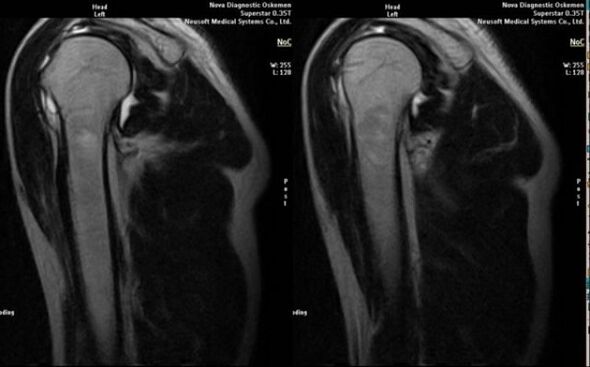

- Magnetresonanz- und Computertomographie;

Anzeichen, die direkt auf die Entwicklung einer Arthrose hinweisen, sind das Auftreten einer deutlichen Verengung des Gelenkraums, Sklerose subknorpeliger Strukturen, Ausdünnung der Chondrozytenschicht selbst, das Auftreten von Osteophyten und die Ablagerung von Salzkristallen in der intraartikulären Flüssigkeit.